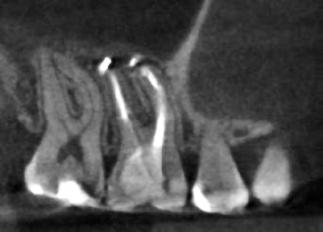

1. ábra: A 15-ös foggyökér meziális felszíne mellett látható radiolucens elváltozás, illetve a felvételen látható a korábban behelyezett gyökértömés, a parapulpális csap segítségével elhorgonyzott csonkfelépítés és a fogat borító cirkonkorona. –2. ábra: A saggitalis irányú CBCT-metszeten jól megfigyelhető az állcsontgerincet elérő radiolucens elváltozás. – 3. ábra: Az axiális irányú CBCT-metszeten egyértelműen látható a kezeletlen palatinális gyökércsatorna, valamint a radiolucens elváltozás mezio-disztális kiterjedése is jól megítélhető. – 4. ábra: A palatinális gyökércsatorna szelektív endodonciai kezelése során először gyógyszeres zárás került behelyezésre. – 5. ábra: A gyógyszeres zárás során alkalmazott kalcium-hidroxid alapú paszta a szulkuszon keresztül a szájüregbe extrudálódott. – 6. ábra: A gyökértömő anyag a középső és apikális gyökéri harmad határán lévő laterális csatornán keresztül a periapikális térbe extrudálódott. 7. ábra: A kezelések befejezését követően 4 évvel készült röntgenfelvételen jól látható a csontállomány gyógyulása és a fiziológiás gyökérhártyarés újbóli kialakulása. –8. ábra: A peroperatív CBCT-felvétel alapján készített koronális irányú metszeten jól látható a gyökércsúcs körül lévő periapikális felritkulás. – 9. ábra: A kezelések befejezése után 4 évvel készített CBCT-felvételen a gyulladásos lézió teljes megszűnése észlelhető.

A CBCT-készülékek endodonciai alkalmazásának talán az az egyik legnagyobb előnye, hogy így olyan anatómiai struktúrák is láthatóvá válnak, amelyeket egyébként nem tudnánk detektálni panoráma, cephalo, vagy periapicalis felvételek segítségével. Mivel a CBCT-felvételek kiértékelése számítógép segítségével történik, így a felvételek vizsgálata során lehetőségünk van az adott területet több nézőpontból és több síkban is megvizsgálni. 2015 októberében egy korábban a rendelőnkben kezelt 55 éves férfi páciens azzal a céllal kereste fel ismét a rendelőnket, hogy másodvéleményt kérjen egy jobb felső kvadránsban található fogával kapcsolatban. Egy másik rendelőben történő vizsgálat során a panaszos fog törését vélelmezték és a fog eltávolítását javasolták, illetve arról is beszámolt, hogy az elmúlt hét során ezen a területen egy puha duzzanat is kialakult. A klinikai vizsgálat során a jobb felső első és második kisőrlő között (14–15) egy fluktuáló duzzanatot észleltünk az áthajlásban. Az 15-ös fog mesialis oldalán 12 mm mély tasakot szondáztunk. A páciens által hozott periapicalis felvételen a 15-ös fog gyökércsúcsának mesialis részén egy nagy kiterjedésű radiolucens elváltozás volt észlelhető (1. ábra). A saggitális síkban vizsgált CBCT-felvételen (Carestream CS 9000, Carestream Dental) a lézió valódi kiterjedése is láthatóvá vált (2. ábra). A megelőző endodonciai kezelések során csupán a bukkális csatorna került detektálásra és gyökértöméssel való ellátásra. Az axiális irányú CBCT-szeleteken egyértelműen látható volt az ellátatlan palatinális gyökércsatorna (3. ábra)

Először kalcium-hidroxid alapú ideglenes gyógyszeres zárás került a palatinális csatornába (UltraCal XS, Ultradent Products; 4–5. ábra), amelyet 6 hét után a végleges gyökértömés elkészítése előtt eltávolítottunk. A gyökértömés elkészítése során meleg vertikális kondenzációs technikát alkalmaztunk. Radiológiai felvételen megfigyelhető volt, hogy a gyökértömő anyag egy laterális csatornán keresztül kis mennyiségben a periapicalis térbe extrudálódott (6. ábra). A 4 évvel később készített kontrollfelvételeken a lézió gyógyulása volt megfigyelhető (7–9. ábra). A vizsgálati eredmények és a kezelés kimenetele egyértelműen igazolta, hogy nem gyökérfraktúrával álltunk szemben, tehát a kezdeti diagnózis tévesnek bizonyult. Ez is azt erősíti, hogy korlátozott mennyiségben rendelkezésre álló adatok alapján nem lehet pontos diagnózist felállítani. Manapság szinte elengedhetetlen a CBCT-felvételek endodonciai beavatkozások során történő használata, feltéve, ha ezek elkészítése során az ALARA elv (as low as reasonably achievable) betartásra kerül.